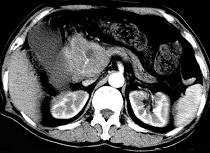

问题 男50岁黄疸进行性加重、腹部胀痛不适、食欲减退、体重减轻、上腹部可触及肿块,CT如图,最可能的诊断为 ( )

选项 A.急性胰腺炎 B.慢性胰腺炎 C.胰头癌 D.腹膜后淋巴瘤 E.转移瘤

答案 C